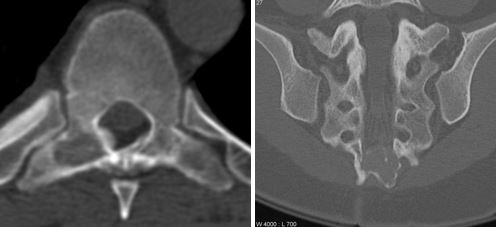

Дегенеративные процессы в позвоночнике

Дегенеративные патологии позвоночника и патологические процессы в мышцах также могут быть причиной образования шишек на позвоночнике. Если шишка похожа на небольшой плотный узелок, который вызывает болевые ощущения при пальпации, речь, скорее всего идет о мышечных узлах. Это точки перенапряжения мышц, возникающие вследствие неврологических нарушений, проблем с опорно-двигательным аппаратом, нарушений осанки – зажатые мышцы оказывают давление на нервные корешки, из-за чего возникают неприятные ощущения.

Дегенеративные патологии позвоночника и патологические процессы в мышцах — еще одна возможная причина

Твердые, костистые отростки в пояснично-крестцовой области часто свидетельствуют о следующих патологиях:

- осложнения остеохондроза – выпадение межпозвоночных дисков, которое прощупывается под кожей;

- нестабильность и смещение тел позвонков;

- деформирующий остеоартроз;

- спондилез, характеризующийся появлением наростов и отложением солей по краям позвонков.

Для справки! При остеохондрозе и его осложнениях наросты на позвоночнике чаще всего образуются на поздних стадиях, и сопровождаются другими симптомами – ограничение подвижности, нарушение чувствительности, болевые ощущения в пояснично-крестцовом отделе, слабость мышц.